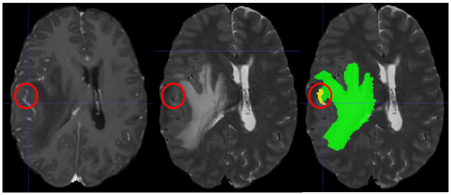

Building upon observations during all previous BraTS instances, we note some common errors in the automated segmentations. The most typical such errors observed are:

1. 1.

The choroid plexus and areas of T1 bright blood products (when they can be discriminated by comparing with the pre contrast T1 images), have erroneously been labelled as ED (Fig. 2(a)).

2. 2.

Vessels within the peritumoral T2 FLAIR edematous area, have been marked as ET (Fig. 2(b)).

3. 3.

Vessels within the peritumoral T2 FLAIR edematous area, have been marked as ED (Fig. 2(c)).

4. 4.

Periventricular white matter hyperintensities being confused and segmented as tumor/peritumoral regions (Fig. 2(d)).

Refer to caption

(a) Choroid plexus erroneously marked as ED.

(b) Vessels in ED marked at ET.

(c) Vessels in ED

(d) Periventricular white matter hyperintensities. Figure taken from [41].

Figure 2: Common errors expected from the automatic segmentations.